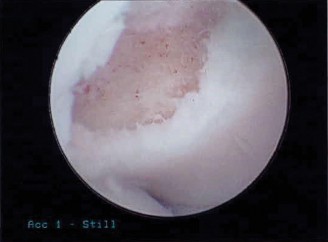

CT arthrograms of the patient’s left shoulder are shown in Figure 2–56. CRP is <3, ESR 45. The patient continues to have pain, so you decide to perform arthroscopic biopsy to obtain tissue cultures. Frozen sections show <5 PMNs per hpf, and Gram stains are all negative.

Figure 2–56

The correct answer is (B). Figure shows contrast under the glenoid component. Given the patient’s normal inflammatory markers and frozen sections combined with continued pain and loosening on CT, infection with P. acnes(an organism that is very difficult to isolate) should be investigated by holding any cultures for at least 2 weeks to see if it will eventually grow. Chocolate agar (Choice C) is mainly used for growing species such as H. influenzae and Neisseria meningitidis not P. acnes. A is incorrect since the patient’s cell count and frozen sections are clearly abnormal, therefore referral to pain clinic would not be appropriate. However, Choice D would be too aggressive an approach given that no organisms have been isolated, frozen sections show <5 PMNs per hpf, and the patient has relatively normal inflammatory markers.